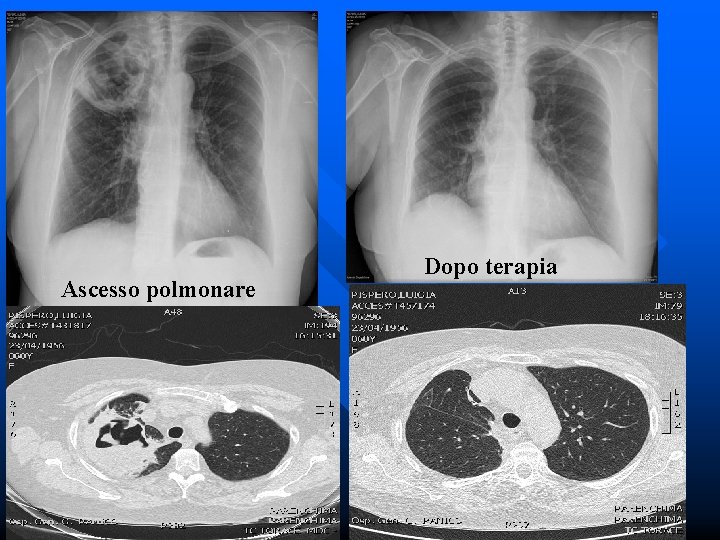

RX: Ascesso lobo sup. dx Immagine TAC

Ascesso polmonare Dopo terapia